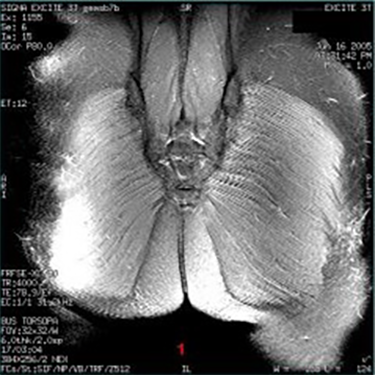

| Dielectric Effect Inhomogeneity/Shading in the image | ![]() | Interaction of matter with electrical component of RF field |